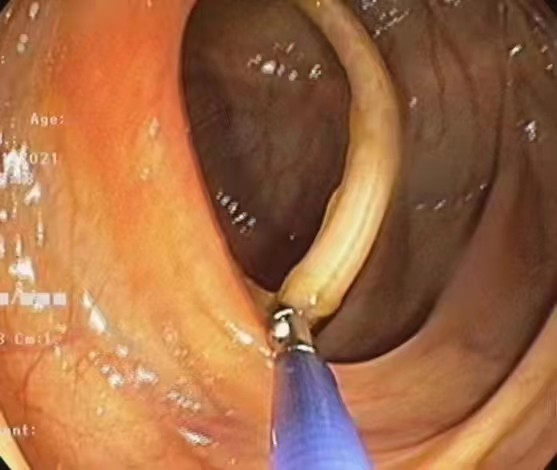

西安莲湖秦华中医医院徐伟医师-内镜下精准取蛔虫!

11月20日下午由徐伟主任为患者闫先生进行肠镜检查,在回盲部发现一条蛔虫,长约20cm,向阑尾开口处蠕动,与患者家属告知病情及沟通后,立即给予异物钳钳夹蛔虫,随镜取出。徐主任表示此次患者行结肠镜检查非常及时,若蛔虫进入阑尾,则患者腹部疼痛剧烈,需住院手术治疗,且肠镜发现蛔虫案例及罕见。患者及家属表示感谢,为徐主任丰富的临床经验点赞。